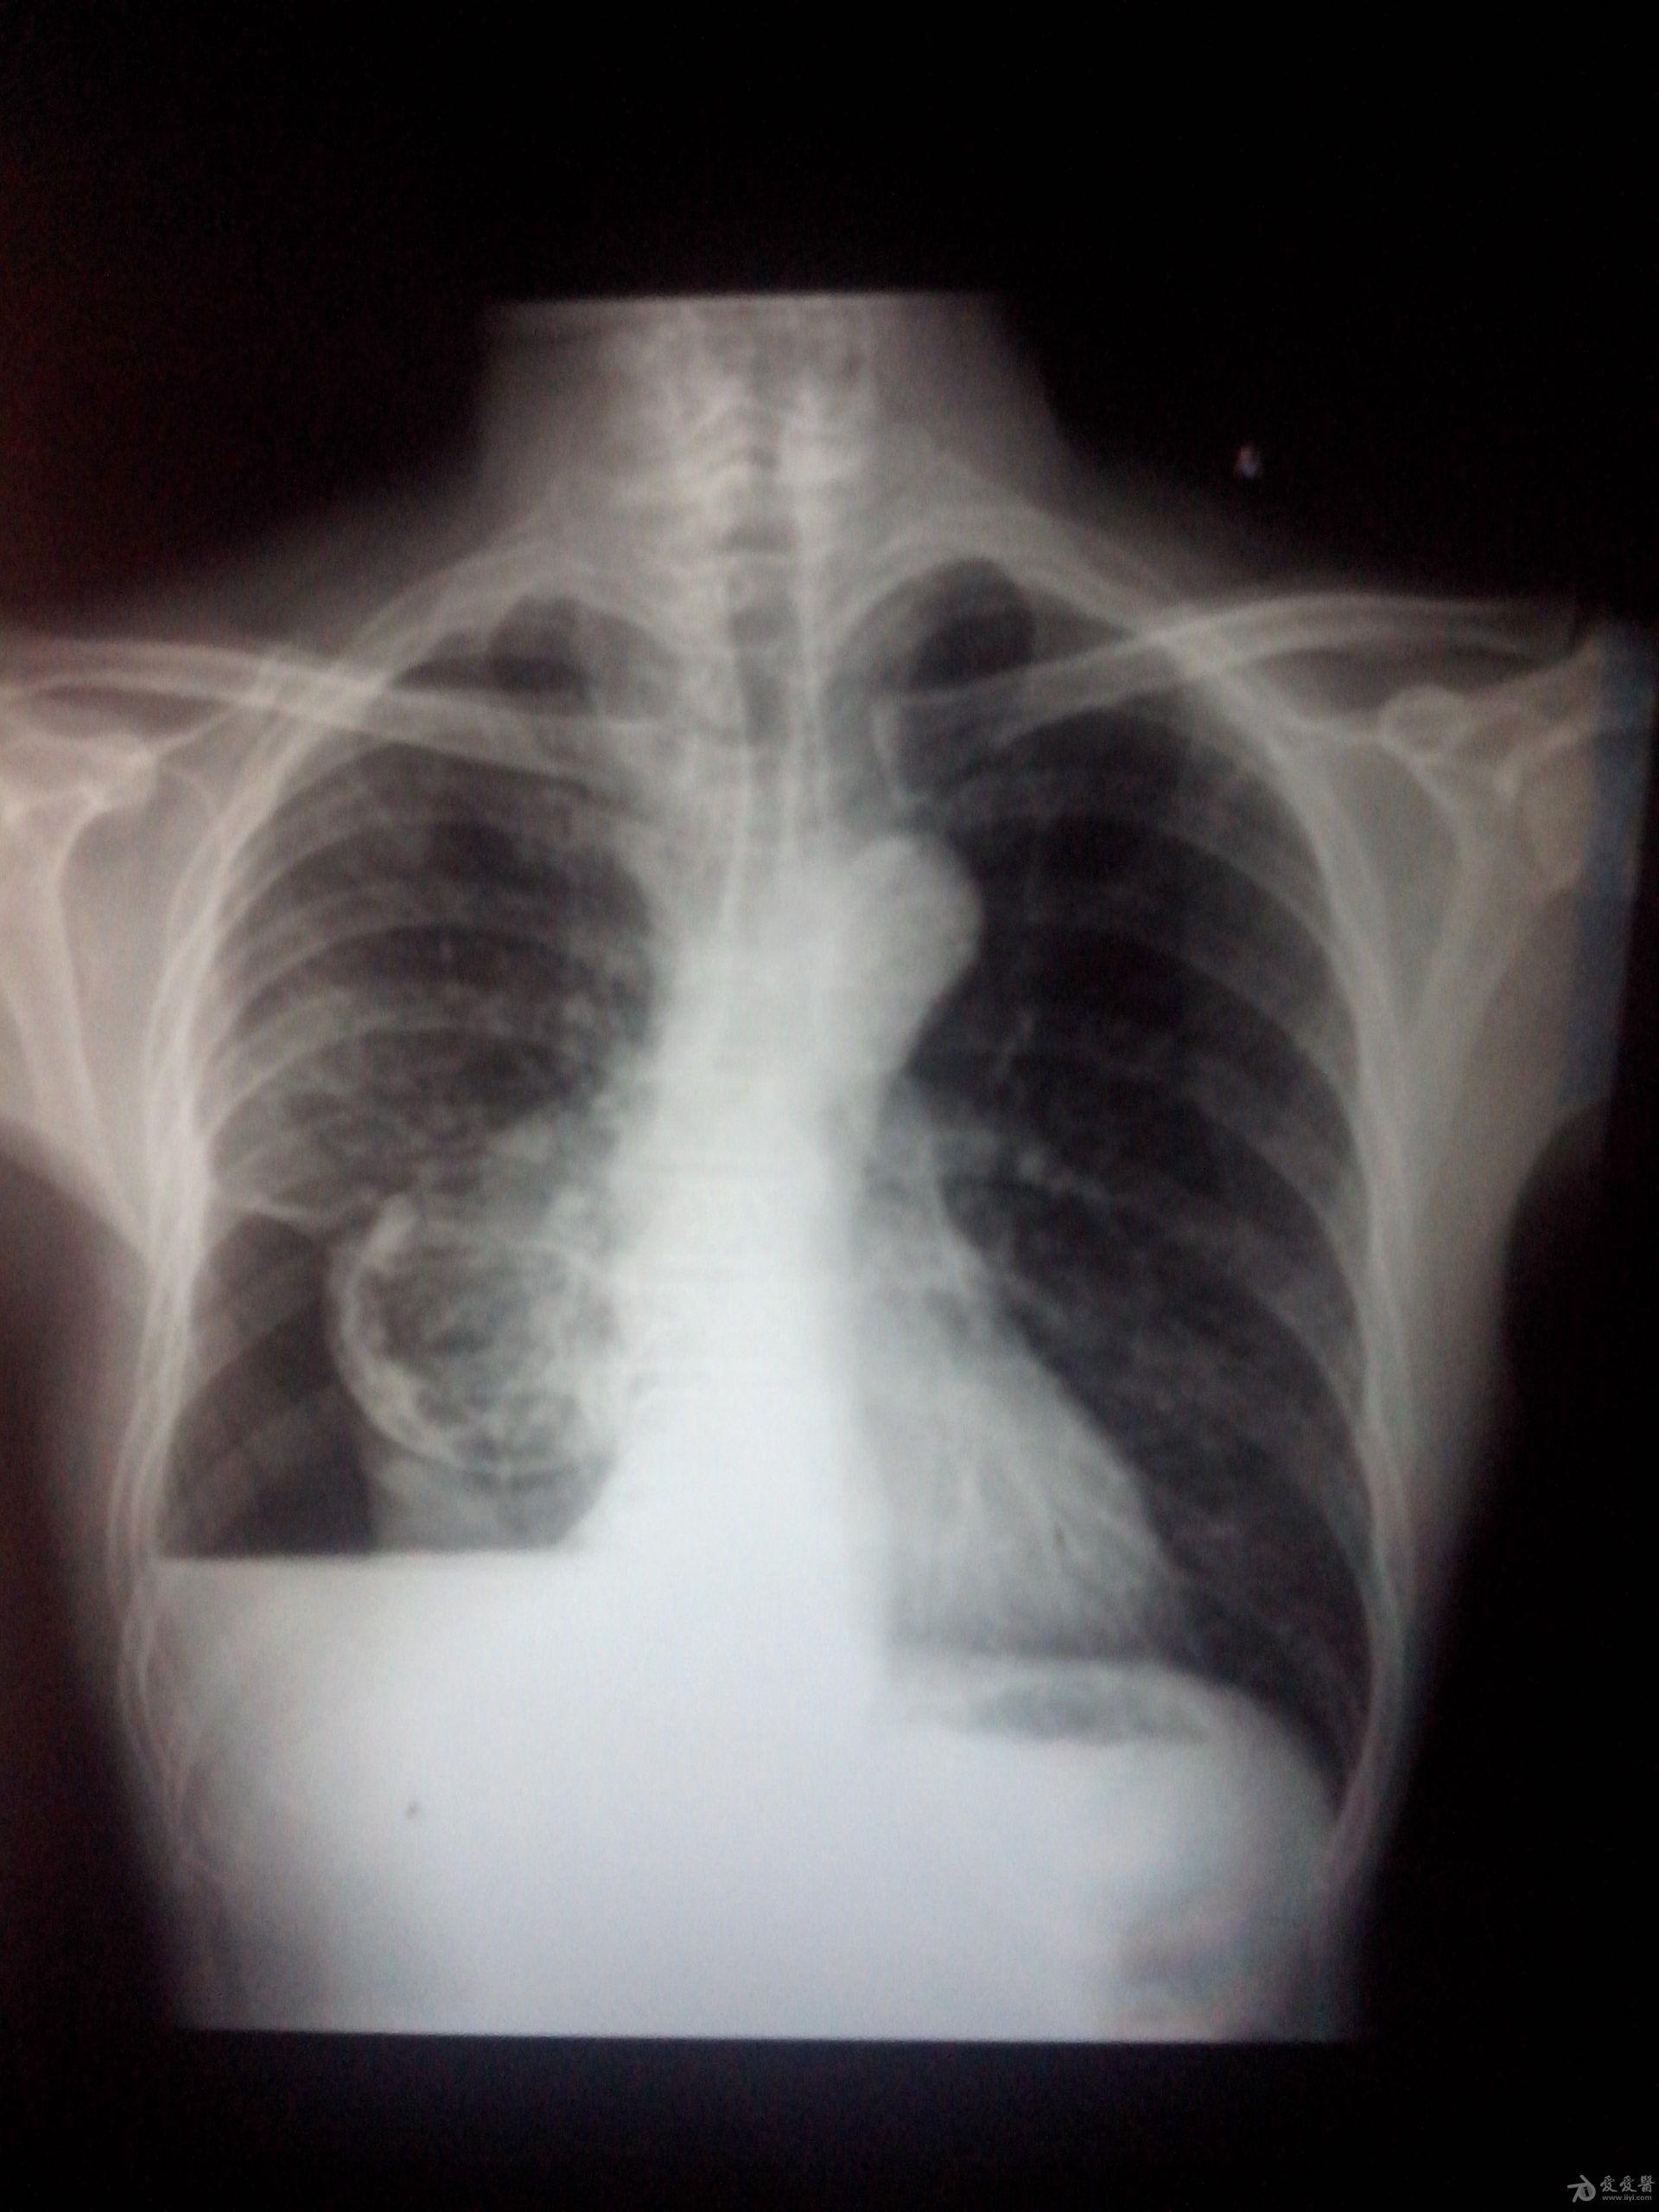

胸片(70岁,男,咳嗽,气喘,发烧,胸腔积液)

患者手术前胸部dr所见心脏位于右侧胸腔